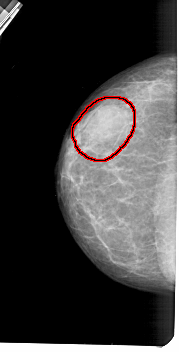

A_1419_1.LEFT_MLO

LEFT_MLO LINES 5491 PIXELS_PER_LINE 2731 BITS_PER_PIXEL 12 RESOLUTION 43.5 OVERLAY

FILE: A_1419_1.LEFT_MLO.OVERLAY

TOTAL_ABNORMALITIES 1

ABNORMALITY 1

LESION_TYPE MASS SHAPE OVAL MARGINS OBSCURED

ASSESSMENT 4

SUBTLETY 4

PATHOLOGY BENIGN

TOTAL_OUTLINES 1

BOUNDARY